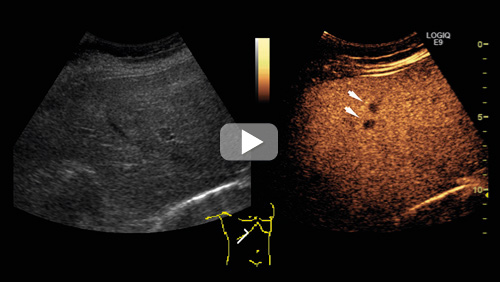

På bildet over til venstre vises et konvensjonelt ultralydbilde gjennom leveren, til høyre det korresponderende kontrastforsterkede bildet. Det kontrastforsterkede bildet er tatt i sen kontrastfase, og man kan se flere typiske metastaser som mørke flekker på lys bakgrunn (se video på nett for fremstilling av hele høyre leverlapp). Eksemplet viser en metastase fra tykktarmskreft. Det er betydelig lettere å identifisere metastasene på de kontrastforsterkede bildene.

Kontrastforsterket ultralydundersøkelse av leveren er en metode for deteksjon og karakterisering av fokale lesjoner. Kontrastmidlet, som består av en oppløsning med gassfylte mikrobobler, injiseres intravenøst. Hver enkelt boble er mindre enn en erytrocytt. Boblene sirkulerer fritt i blodstrømmen inntil de etter noen minutter sprekker og gassen pustes ut.

Kontrastforsterket ultralydundersøkelse inngår nå som ledd i bildediagnostisk oppfølging etter kurativ behandling for kreft i tykktarm og endetarm (1). Denne undersøkelsen har tilnærmet lik sensitivitet som CT-undersøkelse for deteksjon av metastaser – og signifikant høyere sensitivitet enn konvensjonell ultralydundersøkelse (2). Metoden innebærer ingen ioniserende stråling eller bruk av potensielt nefrotoksiske kontrastmidler. Undersøkelsen er brukeravhengig, men i mindre grad enn konvensjonell ultralydundersøkelse. Det kan være varierende grad av innsyn, særlig gjelder det adipøse pasienter. Kontrastmidlet er kontraindisert for pasienter med nylig akutt koronarsykdom eller ustabil iskemisk hjertesykdom.